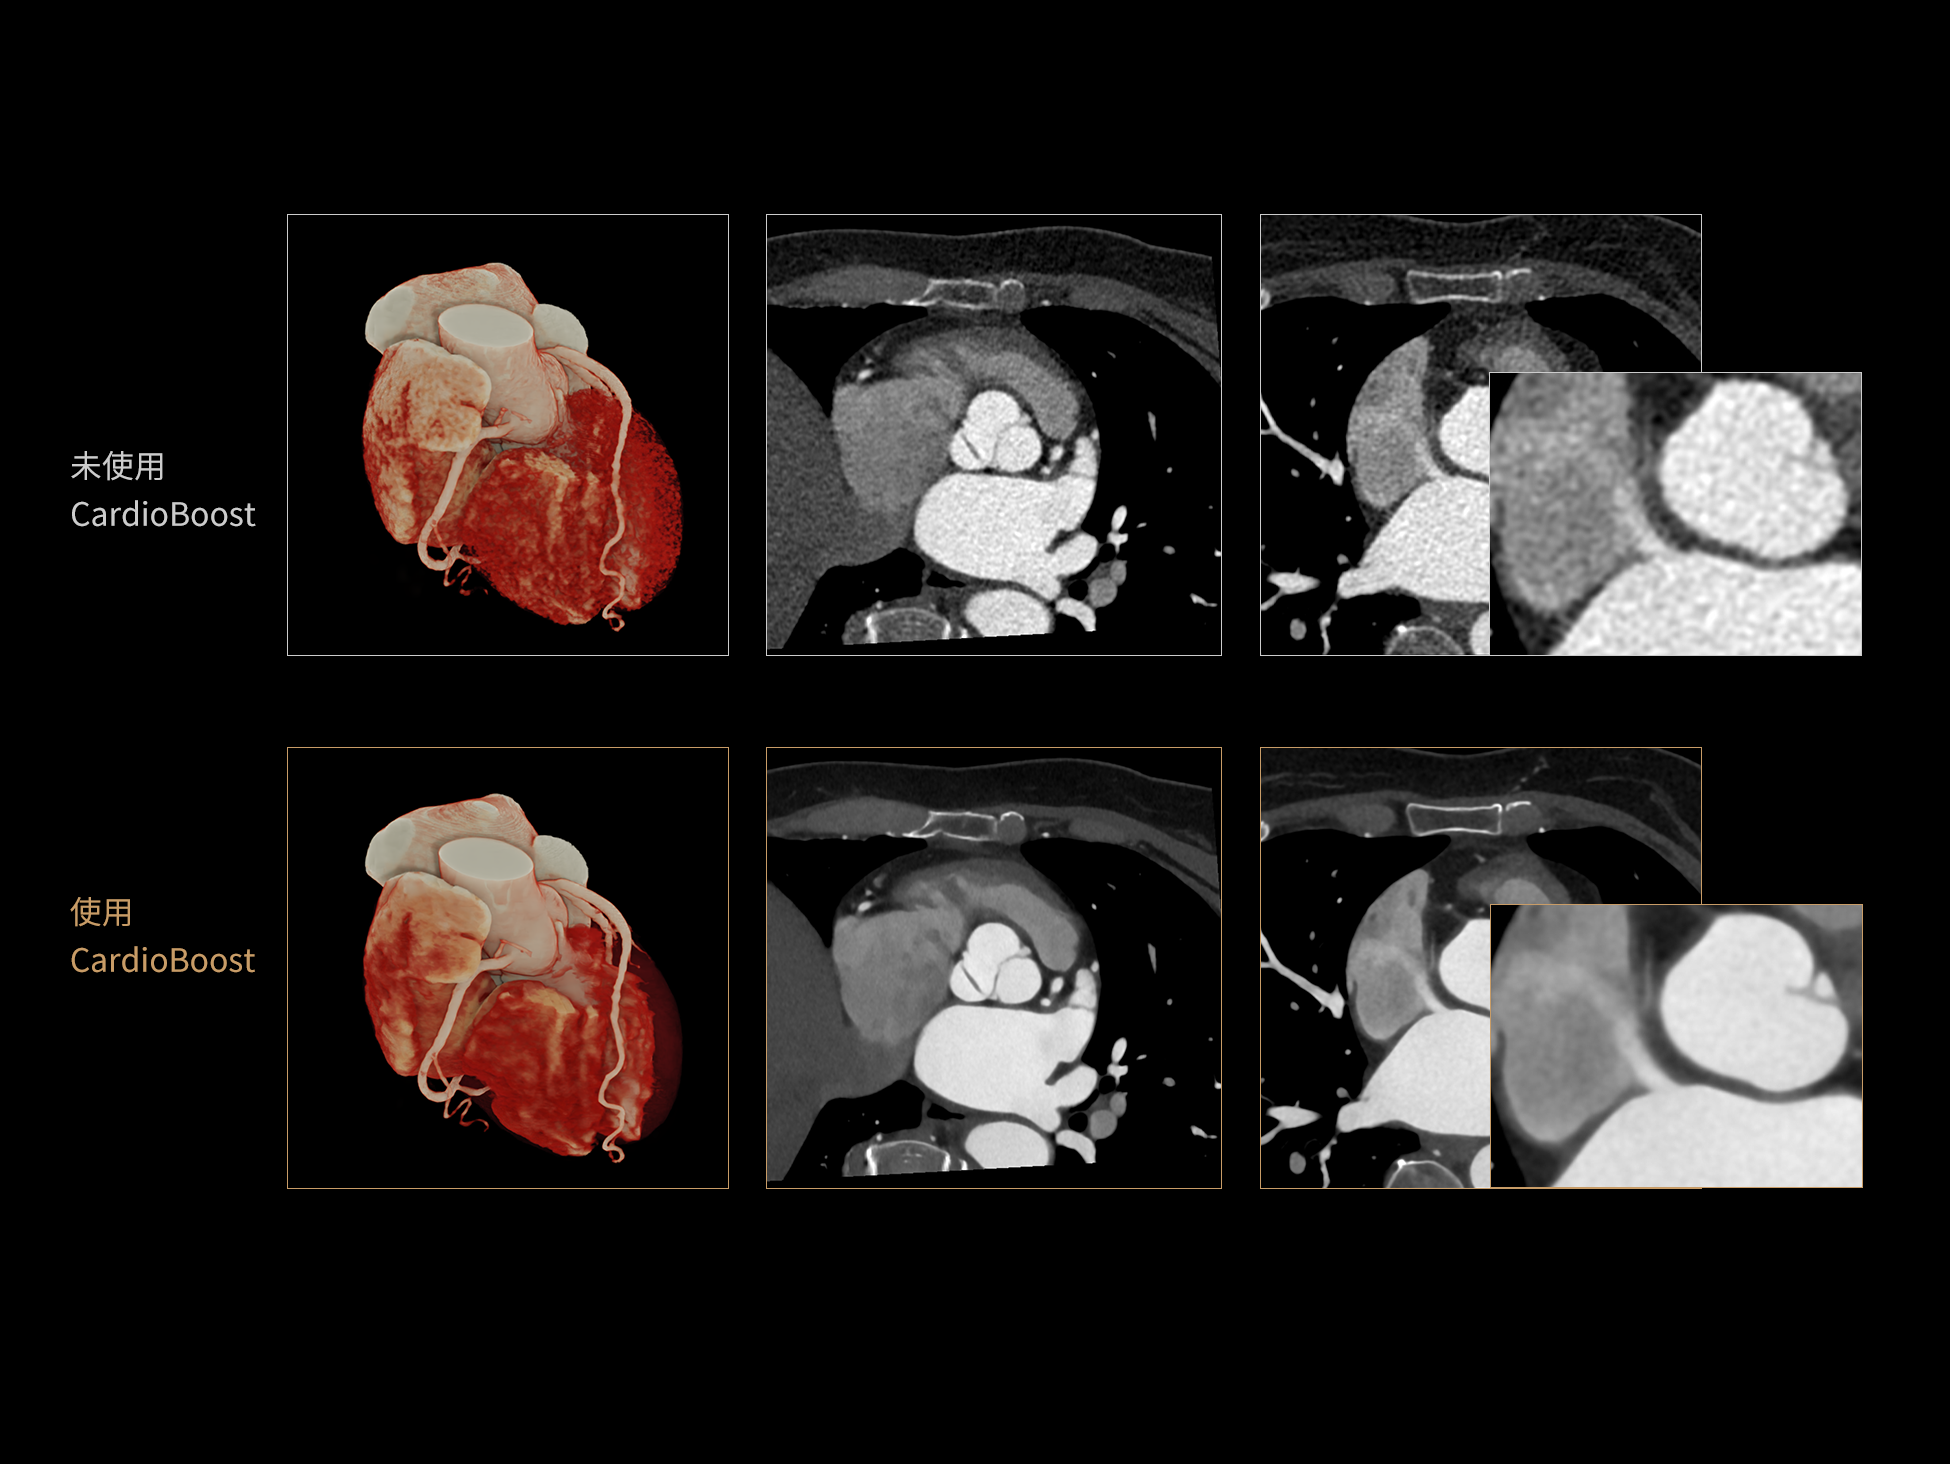

uCT 868 搭载联影最新一代 uSense 人工智能平台,将智能化深度融入 CT 扫描全流程,从感知细微生理运动到精细结构探测,再到多场景诊疗优化。以 AI 为核心驱动力,uSense 重塑成像各环节,打造高效、高清的智慧扫查体验。在心脏成像领域,uSense 结合宽体探测器、心脏专研AI重建算法与AI冠脉运动追焦技术,在保持低剂量的同时,有效抑制运动伪影,精准呈现软斑块、混合型斑块及支架细节,助力冠脉成像惠及更多患者。针对多科室疾病临床应用场景,uSense 平台提供全方位的智能解决方案:包括头部运动伪影智能校正、金属植入物伪影抑制、扫描视野扩展等先进算法。这些创新技术使 uCT 868 能够构建覆盖全场景的智能诊疗体系,持续拓展 AI 赋能医学影像的边界。